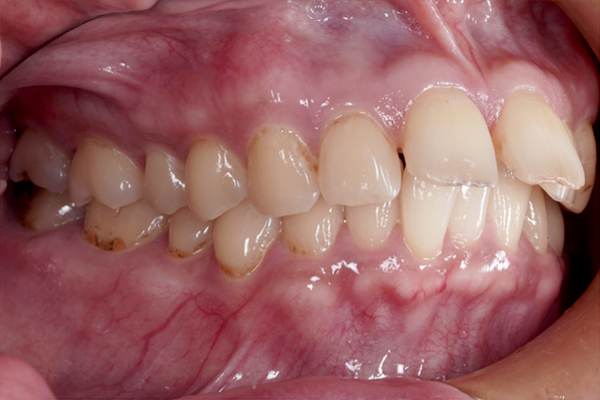

横からの比較(右側)

治療開始から9か月が経過し、前歯の重なりは徐々に改善し、上の前歯も少しずつ後方へ移動しています。見た目にも変化が現れはじめており、治療は順調に進んでいます。

本治療では、インビザラインを用いた非抜歯矯正を行っています。治療の進行にあわせて、インプラントアンカーを使用し、歯を後方へ移動させる計画です。治療期間はおよそ1年6か月を予定しており、現在は開始から9か月が経過した段階です。